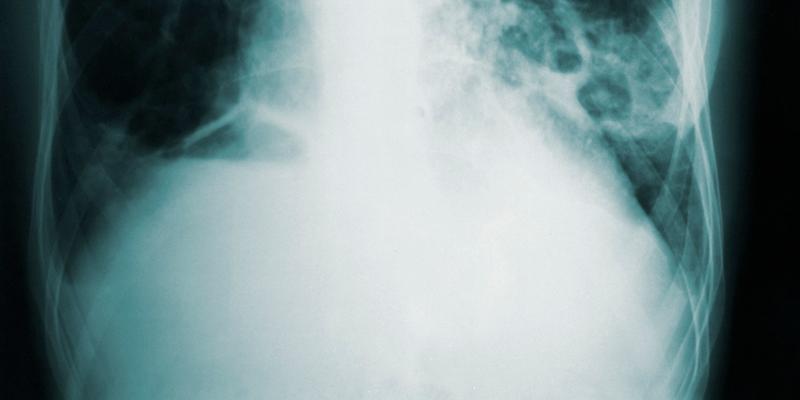

Hallan un tratamiento más eficaz contra la tuberculosis. Foto: @cdc en Unsplash